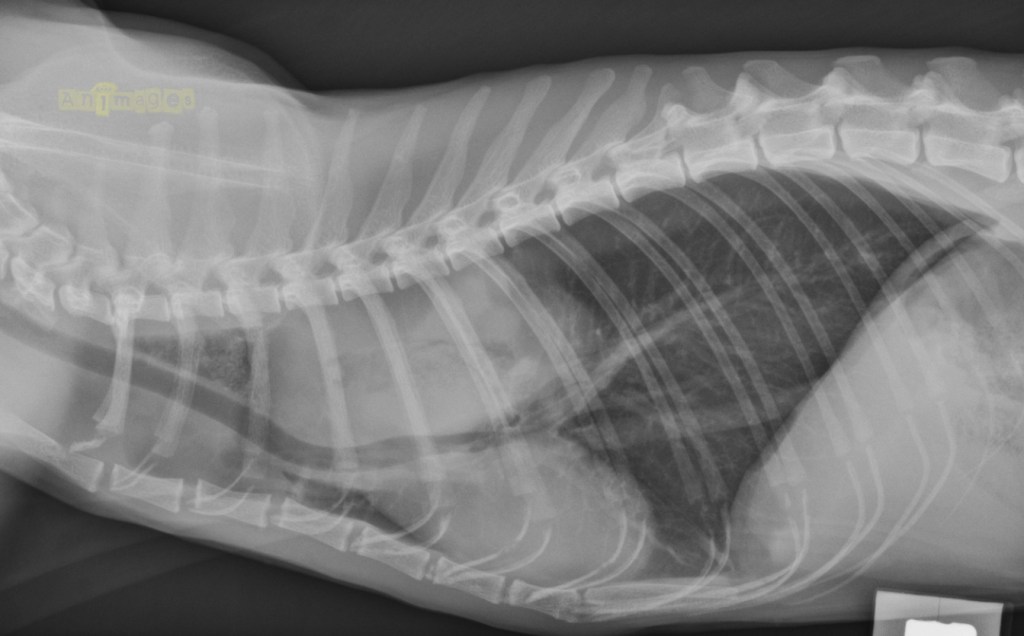

laterale gauche